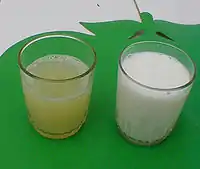

Udder of a Roux du Valais sheep after a healed mastitis; one teat was lost due to the disease. Serous exudate from bovine udder in E. coli mastitis[54] at left. Normal milk at right.

Serous exudate from bovine udder in E. coli mastitis[54] at left. Normal milk at right. Gangrenous mastitis in a dairy cow.